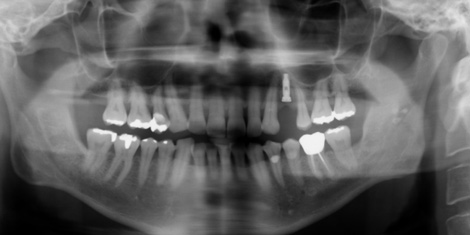

患者さんは今年はじめ赤丸の部位がお痛みで来院しました。

![]() |

レントゲン・歯周病検査で持たせるのは難しいと判断し、患者さんは両隣の健康な歯、特に犬歯(糸切り歯)は削りたくないのでインプラント治療を選択しました。